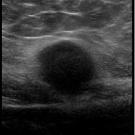

A previously healthy, 13-year-old boy presented to our hospital with a painful mass in the left popliteal fossa. Approximately 3 weeks prior to presentation, he had reported injuring his left lower...

02/24/2023